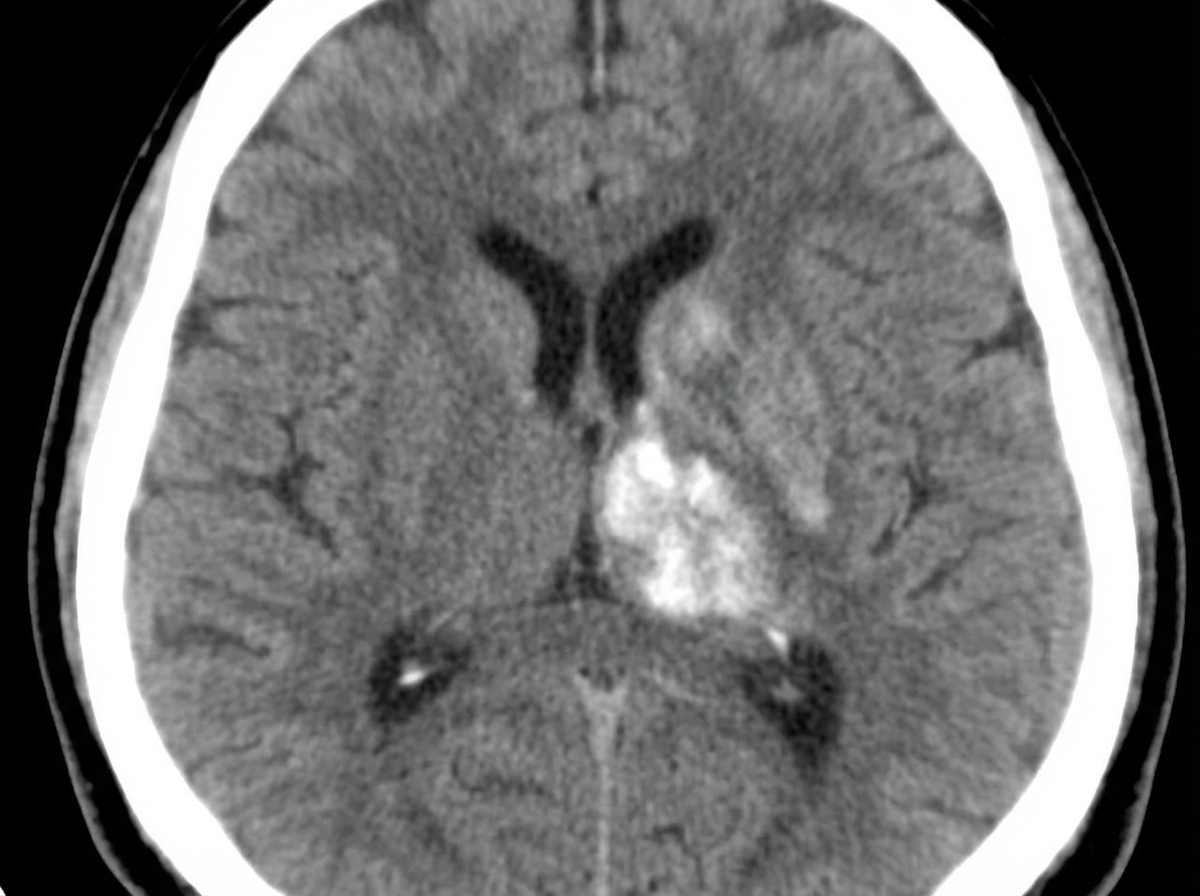

A 63-year-old man complains of worsening headache and right-sided weakness. CT of the head is shown below. What is the most likely diagnosis?

A hypertensive patient was admitted with right hemiplegia. A plain CT scan shows what?

Explanation: ### Explanation **Correct Answer: B. Brain tumor** The clinical presentation of a 63-year-old patient with a **progressive, worsening headache** and focal neurological deficits (right-sided weakness) is highly suggestive of a space-occupying lesion (SOL). On CT, brain tumors typically present as an intra-axial mass with surrounding **vasogenic edema** (finger-like projections), mass effect (midline shift), and potential contrast enhancement. In an elderly patient, the most likely diagnoses are Glioblastoma Multiforme (GBM) or Metastasis. **Why other options are incorrect:** * **Aneurysmal bleed:** This typically presents as a **Subarachnoid Hemorrhage (SAH)**. On CT, it appears as hyperdense (white) blood in the basal cisterns and sulci, presenting clinically as a "thunderclap headache" (sudden onset), not a progressive one. * **Lacunar infarct:** These are small (<15 mm) ischemic strokes in deep structures (basal ganglia/pons) caused by lipohyalinosis. On CT, they appear as small, well-defined hypodense areas without significant mass effect or edema. * **Vasculitis:** CNS vasculitis usually presents with multifocal ischemic or hemorrhagic strokes of varying ages. CT findings are often non-specific or show multiple small infarcts, rather than a single large mass lesion. **NEET-PG High-Yield Pearls:** * **Vasogenic Edema:** Seen in tumors and abscesses; involves white matter and spares gray matter (looks like fingers on CT/MRI). * **Cytotoxic Edema:** Seen in cerebral ischemia; involves both gray and white matter (loss of sulcal-gyral differentiation). * **Ring Enhancement:** Differential includes **MAGIC DR** (Metastasis, Abscess, Glioma, Infarct, Contusion, Demyelination, Radiation necrosis). * **Investigation of Choice:** While CT is the initial screening tool in the ER, **Contrast-enhanced MRI** is the gold standard for characterizing brain tumors.

Explanation: ***Hemorrhage in the left thalamus and internal capsule*** - **Hypertensive hemorrhages** commonly occur in the **thalamus** and **internal capsule**, appearing as **hyperdense** (bright white) lesions on plain CT scan. - Left-sided lesions in these structures cause **contralateral hemiplegia** (right-sided weakness) due to disruption of **motor pathways**. *Hemorrhage in the left frontal lobe* - Frontal lobe hemorrhage would typically cause **behavioral changes** and **personality disorders** rather than pure hemiplegia. - The **motor cortex** involvement would cause more **focal weakness** rather than complete hemiplegia affecting the entire right side. *Ischemic infarct in the internal capsule* - **Acute ischemic infarcts** appear **hypodense** (dark) on CT, but are often **not visible** in the first 24 hours. - Plain CT has **poor sensitivity** for acute ischemic strokes, especially in small vessel territories like the internal capsule. *Ischemic infarct in the left parietal lobe* - Parietal lobe infarcts primarily cause **sensory deficits** and **neglect syndromes** rather than motor hemiplegia. - **Acute ischemic changes** are typically **not visible** on plain CT in the first few hours after symptom onset.